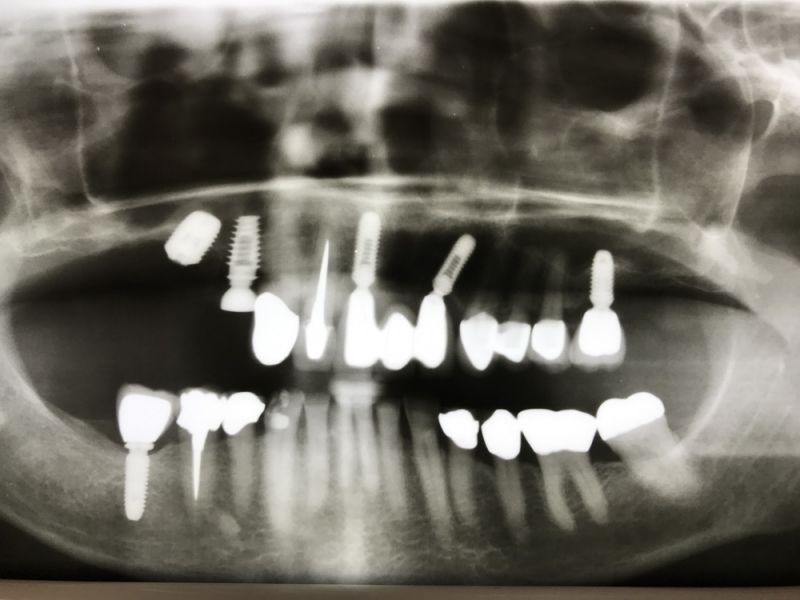

Kieler Patientin zur Versorgung einer Implantatbrückenrekonstruktion

Nach erfolgreicher Osseointegration erfolgt heute die Versorgung der beiden Implantate mit einer Brückenkonstruktion.

Auch in diesem Fall müssen verschiedene Entwicklungsstufen eines Implantatsystems miteinander kombiniert werden.

Das erfordert zum einen die twas aufwändige Beschaffung, weil eben nicht das Verwendung findet, was jeden Tag verwandt wird.

Zum anderenmuss man tatsächlich erst einmal nachdenken, wie das alte System funktioniert.

Es werden alte Schraubendreher mit einem anderen Desingn benötigt und zudem andere Andrehmomente mit den drehmomentgestützten Drehratschen.